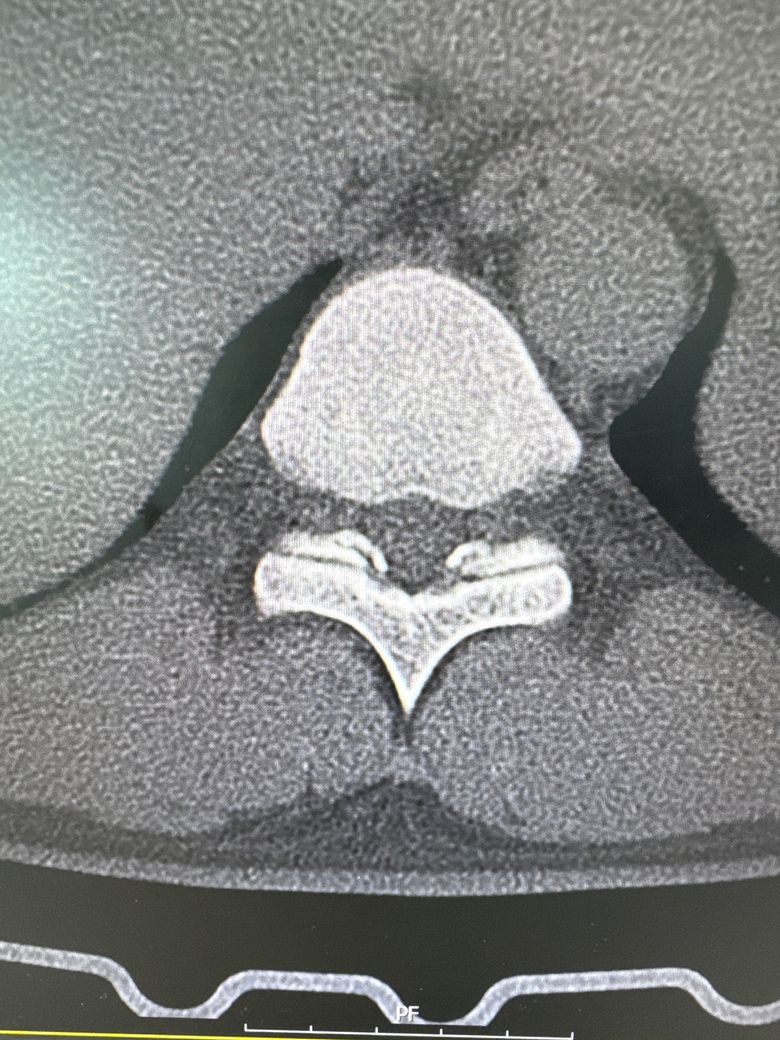

T10/T11쪽인데 신경외과 전문의가 수술할 정도는 아니고 약이랑 블럭주사 정도로 경과를 지켜보자 하셔서 그런데 혹시 대학병원에는 석회를 녹이는 주사나 다른 치료방법이 있을까요? 등은 주기적으로 3~4개월에 아픈데 가끔 등을 삐끗하면 바로 아픕니다ㅜㅜ 9/27일에 MBB맞고 10/23일에 또 맞았는데 오늘이 너무 아팠습니다. 치료방법과 재발 가능성을 낮추는 방법이 있을까요?

• 2번 째 사진